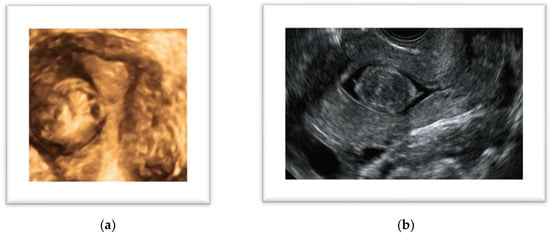

Figure 2.

(a) Three-dimensional ultrasound coronal view of a uterine fibroid; (b) sonohysterography: sagittal view of a G0 (FIGO classification) leiomyoma.

In symptomatic women, sonohysterography can be considered an equivalent diagnostic approach to hysteroscopy, particularly for the localization of submucosal uterine leiomyomas [31], with the advantage over 2D TVS of enhancing the contrast between the myometrium, fibroids, and uterine cavity, thereby helping to differentiate lesions. Sonohysterography involves the distension of the cavity with saline used as a contrast medium, enhancing the relationship between the myoma and the uterine walls and allowing an accurate measurement of the intracavitary part. Sonohysterography should be preferred over hysteroscopy as second-line imaging because it is less invasive, better tolerated, and allows assessment of the size, depth, and vascularization of the entire myoma, whereas hysteroscopy can only visualize the intracavitary portion of the lesion [31]. Three-dimensional TVS, when available, can be a useful tool to exactly locate and measure the myoma by obtaining a coronal view of the uterus, but the relationship with the uterine cavity is not as accurate as per SHG [32]. Furthermore, a 3D scan can be integrated with SHG; however, a recent review reported a sensitivity of 94.5% and a specificity of 99.4% for SHG, with no statistically significant differences between 2D and 3D SHG in detecting intracavitary lesions [33]. One aspect to consider is that fibroids can be associated with pain and AUB, but they can also be implicated in infertility through several mechanisms: they can lead to the distortion of the uterine cavity, alteration of endometrial and myometrial vascularization, interference with uterine contractility, the triggering of hormonal, paracrine and molecular alterations, and impairment of endometrial receptivity [34]. Subserosal fibroids are less likely to be symptomatic; however, they can have various clinical manifestations, potentially causing pelvic pain, urinary discomfort and frequent bladder voiding, venous thrombosis, and low back pain. The symptoms might be related to the specific localization and the size of the myoma. Two specific circumstances deserve specific attention because they may constitute a possible cause of acute pain: the torsion of a pedunculated myoma and the myoma’s necrosis. In the presence of pedunculated leiomyomas, torsion may be a possible consequence of the patient’s movements, although this is a rare complication. The diagnosis is not always simple because the pedicle flow of the myoma, examined through color Doppler, may not be absent [35]. On the other hand, the degeneration and necrosis of a myoma is usually the consequence of rapid growth, and it occurs in large myomas because of blood supply insufficiency in the center of the lesion. This condition typically occurs in large myomas during pregnancy where they are likely to grow up to 20% in volume in the first 16 weeks. A peculiar localization of myomas is between the sheets of the broad ligament or the parametrium; lesions with this characteristic are defined as infraligamental myomas (FIGO 8) [21,36]. Occurring in only 6% of cases, these fibroids are quite rare, but the diagnosis is important because their surgical removal can be challenging and is associated with a higher risk of ureteral and uterine artery injury. As these fibroids are often retroperitoneal, ureteral dissection and identification of the uterine artery at the origin are often necessary to avoid complications [36].